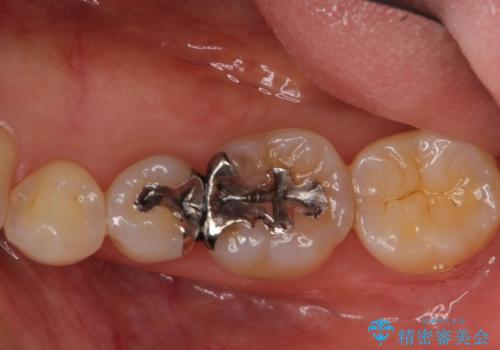

- 銀の詰め物が気になるとのことで来院。

2本隣り合っているつめものを、同時にやりかえをしました。

- 14万円(左下5・左下6 emaxプレスインレー 7万円 x 2)費用は治療当時の料金となります